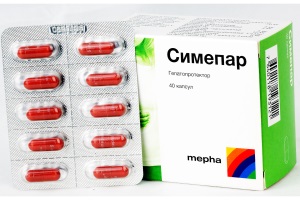

Силімарин та його похідні ще з давніх часів застосовують як гепатопротектори. Гастроентерологи та терапевти широко використовують ці засоби у повсякденній практиці, адже поширення патології печінки в усьому світі набирає обертів.

На сьогодні однією із найактуальніших проблем гепатології є терапія хронічних захворювань печінки.

Мы все хорошо знаем, как сложен и долог путь лекарственного препарата от производства до клиники. Не каждый препарат выдержит проверку экспериментом, временем, а самое главное – практикой.